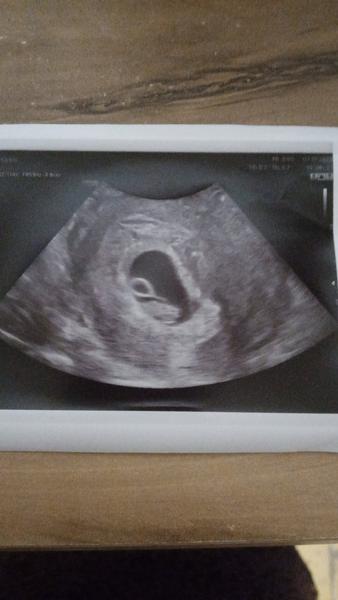

@isabelagrassleova tady je, srdíčko mu tluče a měří 7.5mm dle dr odpovídá 7+1 🥳 dekuju za podporu, zítra čekám info o hcg ❤️